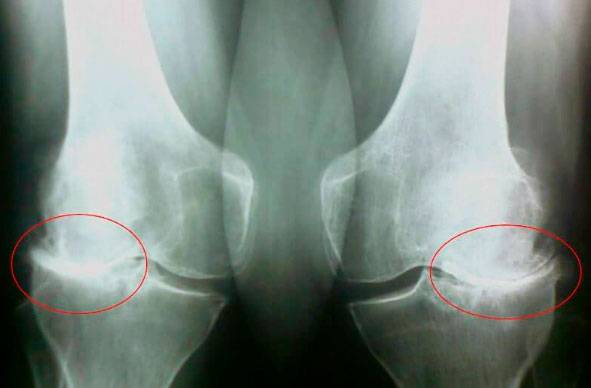

Guarda queste immagini, puoi vedere che nell'immagine a destra manca lo spazio articolare, le ossa si sfregano tra loro e causano un dolore intenso. E questo processo è molto difficile da fermare! Dopo un paio d'anni, una persona sarà disabile e non sarà in grado di prendersi cura di se stessa.